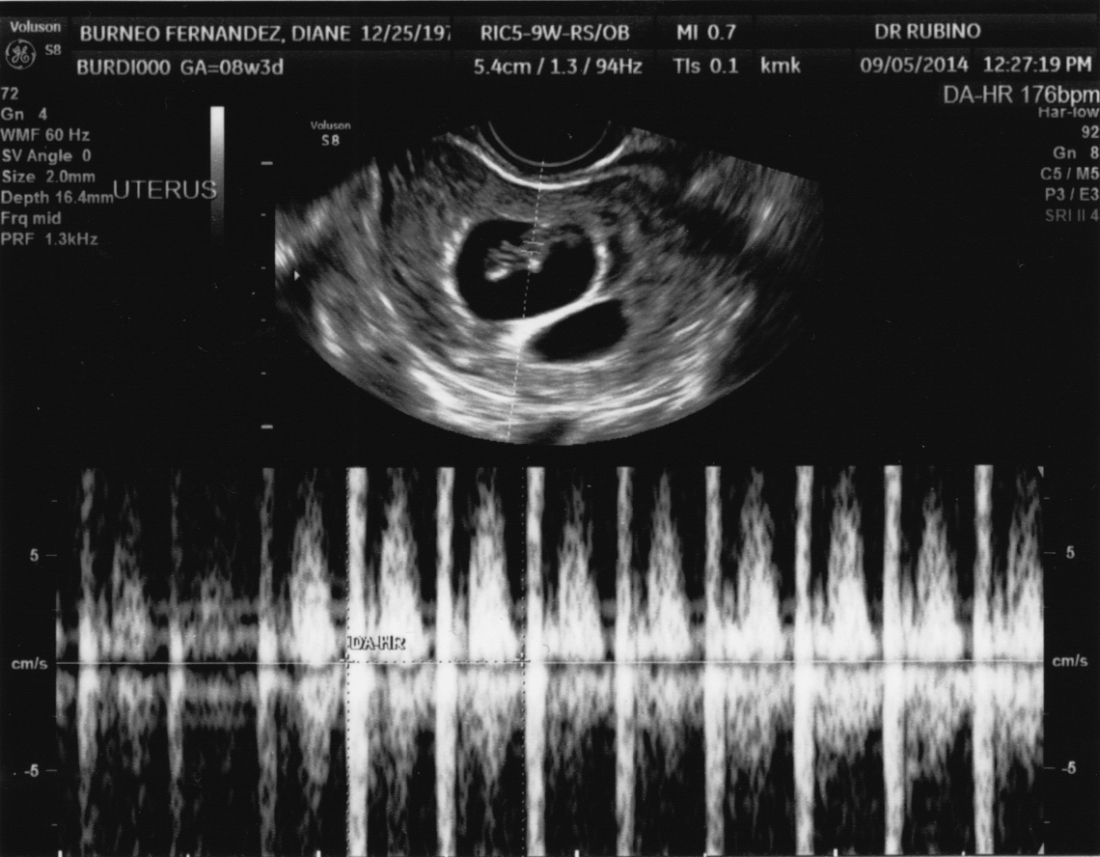

A Fast Beating Heart

My First Ever Picture!

DATE: 05-Sep-2014 TIME: 12:26:22 PM

Taken by a friendly nurse at St. Barnabas Medical Center, in South Orange, NJ, who wanted to charge dad $100 to enter the examination room and see “the show”! Already a big baby, 1.79 cm (0.70 inches) tall!

Why don’t these machines take pictures in color? Or do they?